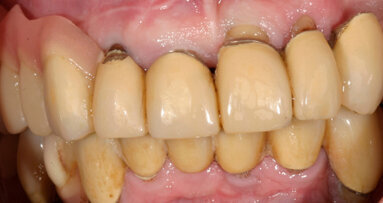

Nei casi di atrofie marcate, è fondamentale ricostruire l’osso mancante ma anche poter dare all’arcata una forma ideale. In questo caso clinico la paziente si presenta alla mia osservazione con una marcata atrofia del mascellare superiore (Fig. 1). La valutazione clinica è stata effettuata con esami radiografici di routine, OPM ed endorali, ma soprattutto con una Cone Beam TC. Da alcuni anni infatti, effettuo tutte le valutazioni diagnostiche in ambiente CAD con un software di chirurgia computer guidata che consente di valutare l’osso residuo in relazione al posizionamento tridimensionale dell’impianto protesicamente guidato.

L’approccio è quello di duplicare la protesi mobile utilizzata quotidianamente dalla paziente per renderla, attraverso punti di repere radiopachi, protesi radiologica. La paziente eseguirà la Cone Beam con la protesi radiologica e grazie alla presenza dei punti di repere radiopachi si potrà fare il matching tra i dati DICOM e la protesi della paziente (Figg. 2-4). Durante questa prima valutazione risulta evidente l’assenza di osso attorno agli impianti. La marcata perdita ossea è prevalentemente orizzontale e si estende in senso antero-posteriore su tutta l’arcata mascellare. Nella zona degli incisivi il posizionamento protesicamente guidato non è possibile a causa dell’assenza orizzontale dell’osso. Nelle zone posteriori inoltre si evidenziano i prolassi dei seni mascellari che riducono ulteriormente la disponibilità ossea. Di fronte a un quadro clinico così complesso si rende necessaria una scelta oculata della tecnica ricostruttiva adeguata.